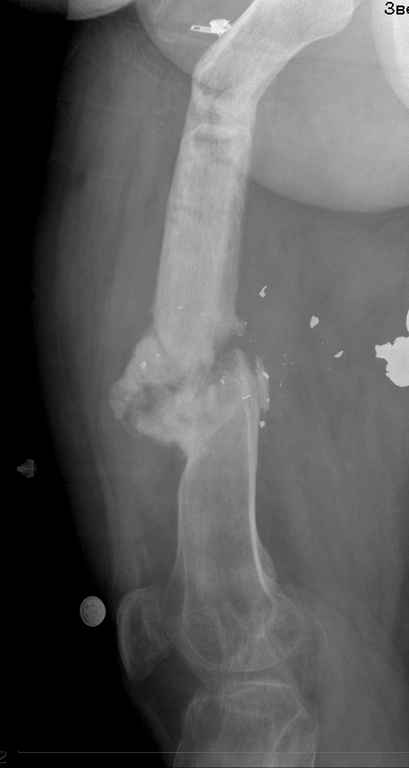

пациент имеет ложный сустав бедра после огнестрельного перелома и длительного лечения Пациент: 48л. ****** (ВРАЧ!) Инвалид 2 группы 3 степени Не работает Жалобы пациента: на невозможность полной нагрузки на левую нижнюю конечность, боли в левом бедре при движениях, в покое, патологическую подвижность в средней трети левого бедра, деформацию и укорочение конечности. Анамнез заболевания. : пациент получил открытый многооскольчатый огнестрельный перелом средней трети левой бедренной кости 24.12.2005г.. В экстренном порядке выполнялась хирургическая обработка раны левого бедра, наложение спице-стержневого аппарата внешней фиксации на левое бедро с вынужденным укорочением сегмента ввиду разрушения и отсутствия костных фрагментов. В послеоперационном периоде рана заживала вторичным натяжением удовлетворительно,без нагноения, выполнялась аутодермопластика дефекта кожи. Фиксация в спицестержневом аппарате в течение 5 месяцев. Правильной репозиции не удалось достигнуть. 24.5.06г. пациент в госпитале Самарского военно-медицинского института повторно прооперирован с установкой спице-стержневого аппарата на бедро и проведением остеотомии в в\3 бедра. Фиксация в аппарате в течение 19 месяцев. Ходил с дозированной нагрузкой на ногу. После снятия аппарата при увеличении нагрузки появилась варусная деформация бедра в зоне остеотомии, признаки образования тугого гипертрофического ложного сустава н\3 бедра. Анамнез жизни. Пациент аллергии на лекарственные препараты не отмечает. Туберкулез, вирусный гепатит, венерическую патологию отрицает. Гемотрансфузии были. Из перенесенных заболеваний отмечает калькулезный холецистит, оперирован в 2006 году – холецистэктомия, осложнившаяся перивезикулярным инфильтратом. Оперирован повторно. – ревизия, дренирование бр.полости. Аппендэктомия в 1993 году. прошу обсудить возможность восстановительного лечения, ПАЦИЕНТ НАСТОЙЧИВО ОТКАЗЫВАЕТСЯ ОТ АППАРАТЕ ВНЕШНЕЙ ФИКСАЦИИ, ИМЕЕТ БОЛЬШОЕ ЖЕЛАНИЕ ДОНОМОМЕНТНОГО ОСТЕОСИНТЕЗА С УСТРАНЕНИЕМ ДЕФОРМАЦИИ И УДЛИНЕНИЯ..

посылаю снимки отдельно

такое ощущение, что пациента на предыдущих этапах лечили только по снимкам нижней трети бедра в прямой проекции.

Учитывая огнестрельный характер перелома, я бы воздержался от транспорта остеотомированного фрагмента на штифте. гораздо надежнее, проще в техническом, а еще, и немаловажно, в финансовом плане (пациент неработающий инвалид) устранить деформации и укорочения в АВФ, а потом быстренько на рассверливаемый штифт, лучше с антибактериальным цементным покрытием.